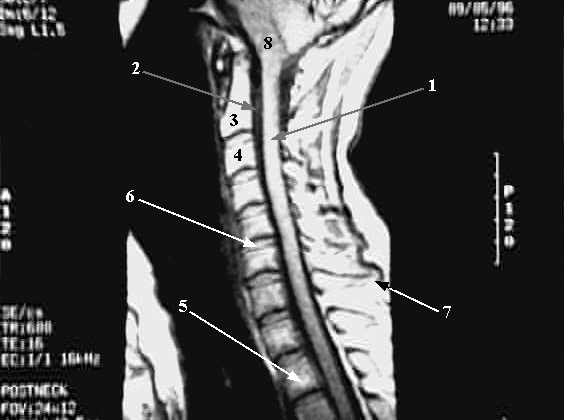

- Spinal Cord

- Subarachnoid Space

- Body of Second Cervical Vertebra (Axis)

- Body of Third Cervical Vertebra

- Body of Second Thoracic Vertebra

- Intervertebral Disc between C5-C6

- Spinous Process of 7th Cervical Vertebra ( Vertebra Prominence)

- Medulla Oblongata.